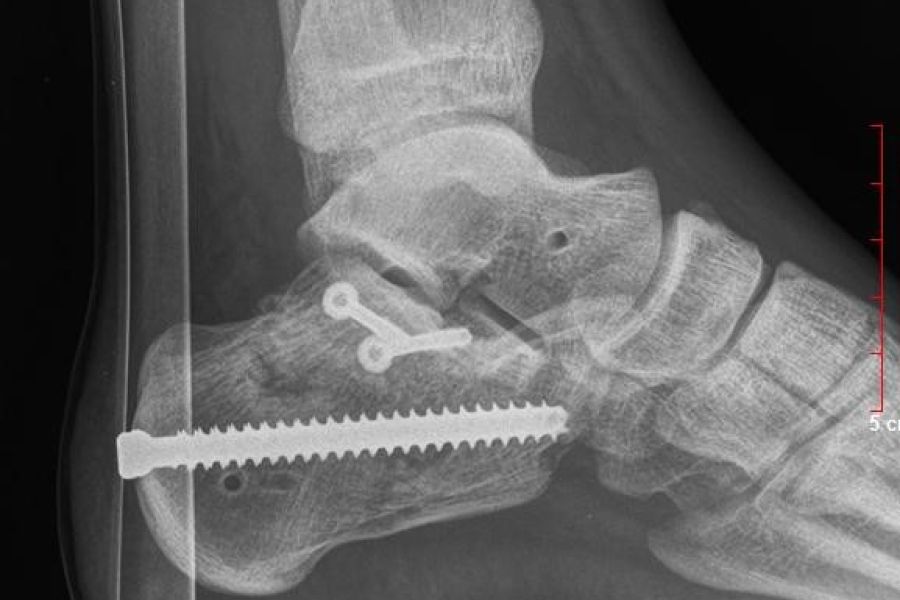

Nach Unfällen (Knochenbrüchen, Muskel-, Sehnen- und Bandverletzungen etc.) ist Physiotherapie wichtig, um den optimalen Heilungsverlauf zu unterstützen. Dabei sollen durch passive Techniken (z.B. Lymphdrainage, Manuelle Therapie, Faszien- und Bindegewebstechniken, Massagen, usw) sowie aktive Bewegungstherapie Schmerzen gelindert, die Beweglichkeit verbessert, Kraft aufgebaut und somit eine möglichst rasche Wiedereingliederung des Patienten in den Alltag erreicht werden.